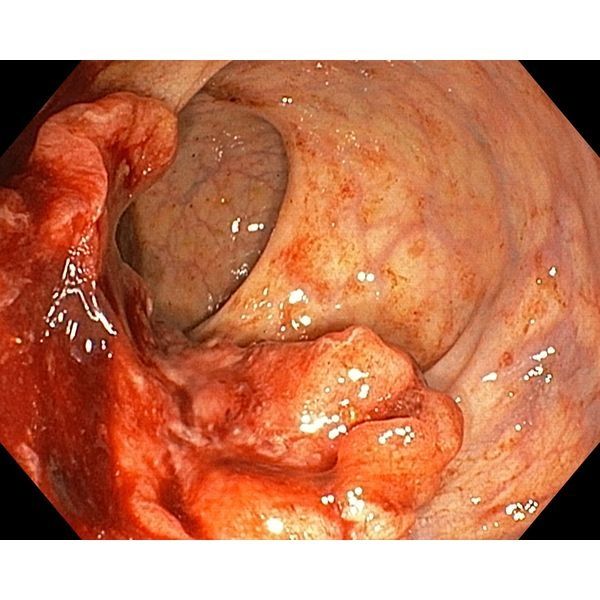

При проведении колоноскопии в январе 2022 года обнаружили полип сигмовидной кишки и злокачественную опухоль прямой кишки. На УЗИ, КТ и МРТ брюшной полости и малого таза метастазы не выявили.

C20. Злокачественное новообразование среднеампулярного отдела прямой кишки. Стадия T3cN1acM0 (опухоль проросла через мышечную стенку прямой кишки в окружающие ткани на значительную глубину, поражён один регионарный лимфоузел, отдалённых метастазов нет). Хроническая анемия лёгкой степени тяжести.